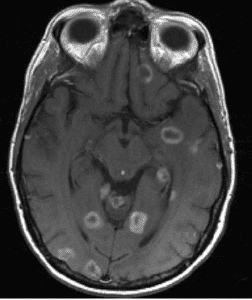

Brain Metastases Assessments

Brain metastases from common solid tumors are frequently seen—they are present in up to 50% of patients with lung cancer, breast cancer and melanoma.

CT scanning is less sensitive than MRI for detection of brain metastases, thus brain MRI is strongly recommended in clinical trials when response determination in brain metastases is required. It is Perceptive’ recommendation that the minimum MRI requirements be consistent with respect to:

6. Follow efficacy criteria for brain metastases

Target lesion selection and measurement

▶ Size: ≥ 10mm in long axis and short axis 5mm

▶ Contrast enhancing

▶ Clear and reproducible lesion boundaries

▶ Avoid selecting necrotic or cystic lesions as target lesions if other solid lesions are present

▶ Measure on axial plane, preferably postcontrast T1w

▶ Slice selection: the slice with the longest inplane diameter should be chosen at baseline for each target lesion’s measurement

▶ Maximum of 5 brain parenchyma lesions

▶ Calculate the Sum of Diameters (SOD) which is defined as the sum of the longest axes of all target brain lesions